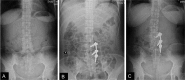

Conclusion: Two-level unilateral instrumented TLIF is an effective and safe method with reduced operative time and blood loss for multiple-level lumbar diseases. But it is imperative that the larger cage should be appropriately positioned to support the contralateral part of the anterior column by crossing the midline of the vertebral body.